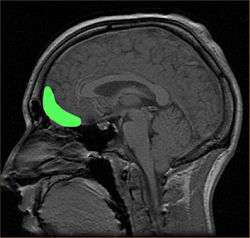

Anatomy and functions

The frontal lobe contains the precentral gyrus and prefrontal cortex and, by some conventions, the orbitofrontal cortex. These three areas are represented in both the left and the right cerebral hemispheres.The precentral gyrus or primary motor cortex is concerned with the planning, initiation and control of fine motor movements dorsolateral to each hemisphere.[20] The dorsolateral part of the frontal lobe is concerned with planning, strategy formation, and other executive functions. The prefrontal cortex in the left hemisphere is involved with verbal memory while the prefrontal cortex in the right hemisphere is involved in spatial memory. The left frontal operculum region of the prefrontal cortex, or Broca's area, is responsible for expressive language, i.e. language production. The orbitofrontal cortex is concerned with response inhibition, impulse control, and social behaviour.[13]